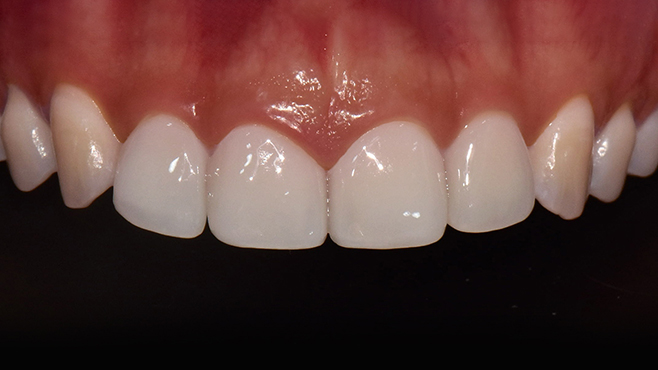

맞는 건 괜찮은데… 충치는 못 참겠습니다|20대 격투기 선수 치과 방문기